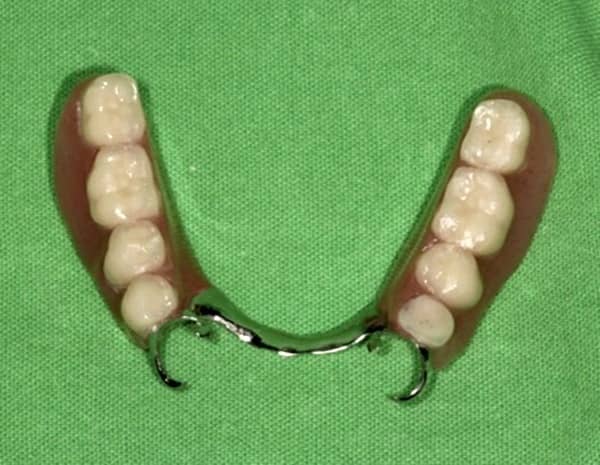

Az alsó állcsontra készült fogpótlásnál jól megfigyelhetők az öntött kapcsok.

Apcsos részleges lemezes fogpótlás alsó